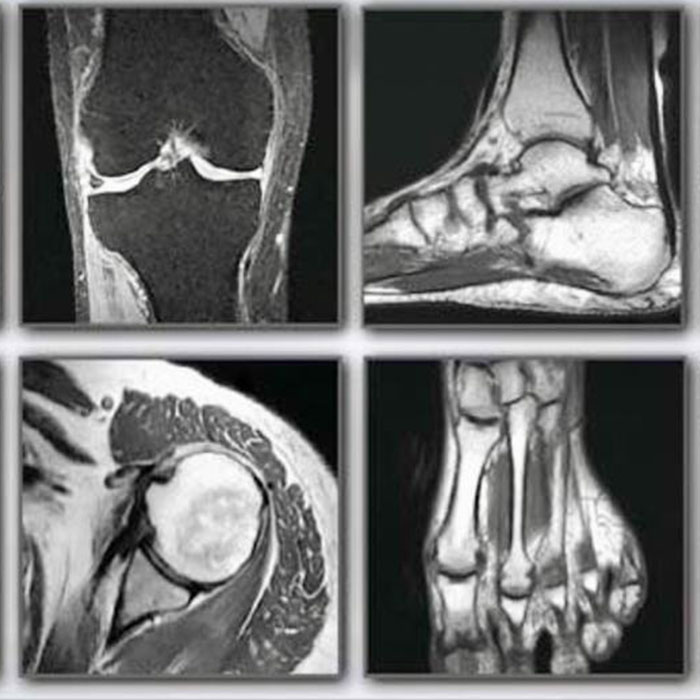

Özellikle, son yıllarda gelişen yeni teknolojiler ile birlikte kas iskelet radyolojisinde kullanılan görüntüleme yöntemlerinde çok fazla değişiklik yaşanmıştır. İleri teknolojiler, daha hızlı ve kesin sonuçların alınmasını sağlarken, hastalar için riski en aza indirgemektedir. Kas iskelet radyolojisi hizmetleri kapsamında radyografi, ultrason, bilgisayarlı tomografi, manyetik rezonans görüntüleme gibi pek çok farklı özel yöntem tercih edilebilmektedir. Üstelik, kas iskelet sistemi incelemelerinde sunulan görüntüleme yöntemleri birbirinin tamamlayıcısı da olabilmektedir. Bu nedenle bir cihaz ile elde edilen görüntüler, başka bir cihaz ile yapılan çekimler ile desteklenerek daha kesin sonuçlara ulaşılabilmesi mümkün olmaktadır.

Kol, bacak, el ve ayak gibi kas ve iskelet sisteminin bulunduğu tüm bölgelerdeki problemlerde, kas iskelet radyolojisi devreye girmektedir. Bu bölgelerde yaşanan rahatsızlıkların neden kaynaklandığı yapılacak ileri tetkikler ile birlikte tespit edilebilmektedir. Kemik ve yumuşak doku bölgelerinin incelenmesi, tümör gibi oluşumların başlayıp başlamadığının kontrol edilmesi, kemik iltihapları, kas yırtılmaları, röntgen ile elde edilemeyen gizli kırıklar ve damar hastalıkları gibi ileri tetkik gerektiren durumlarda kas iskelet radyolojisi kapsamında özel MR’lar çekilerek durum kontrol edilebilmektedir.